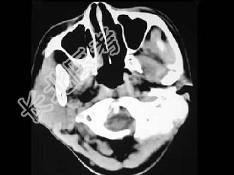

- 单项选择题女,19岁, 右侧面颊部肿胀1年,CT检查如图所示, 最可能的诊断是 ( )